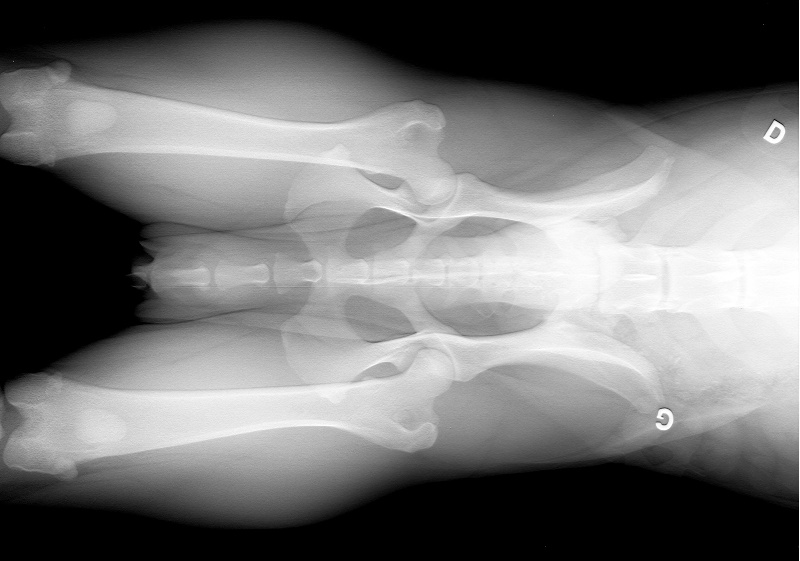

ETALON RADIOGRAPHIE DES HANCHES B ( a/b) c est a dire normal !!!!!

PROGNATHISME : jointif parfait dentition : complete dysplasie des hanches : (A /B) donc B ( lecture offielle) |